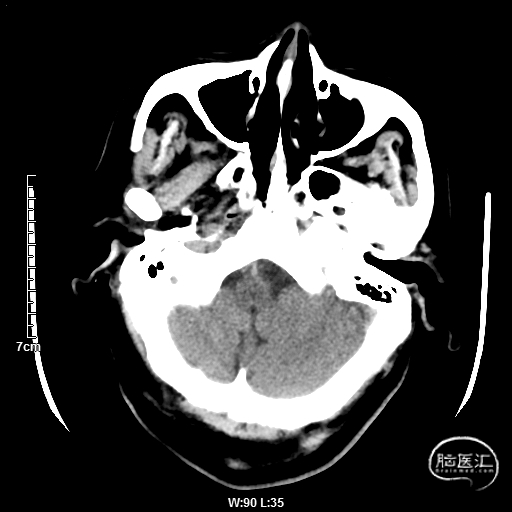

颅脑CT:未见明显缺血/出血病灶。

CTA提示:右侧椎动脉纤细,左侧椎动脉V1、V4段纤细。

MRI提示小脑缺血性改变。

术后CT:未见明显脑出血,双侧小脑低密度影。